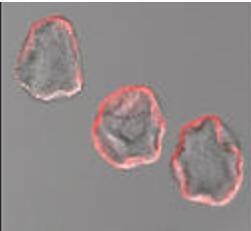

Un nouveau système permettant la diffusion ciblée des facteurs de croissance. Les chercheurs ont alors envisagé l'utilisation de microcapsules, préparées à partir d'alginate. Sur un modèle de rat atteint d'insuffisance cardiaque chronique induite par ligature coronaire (n = 14 à 15 rats par groupe), ils constatent que la libération lente dans le muscle cardiaque de ces facteurs de croissance par microcapsules stimule puissamment l'angiogenèse et l'artériogenèse, prévient l'hypertrophie cardiaque et la fibrose conduisant à des résultats cardiaques améliorés après 3 mois.

Non seulement cette combinaison de facteurs de croissance peut constituer un nouveau traitement efficace pour l'insuffisance cardiaque chronique mais ce nouveau système de diffusion par microcapsules permet d'aboutir au développement de vaisseaux fonctionnels. "Cette combinaison, libérée par des microcapsules administrées directement dans le muscle cardiaque, stimule la croissance de vaisseaux sanguins cardiaques stables et fonctionnels" conclut Ebba Brakenhielm, chercheuse à l'Inserm et principal auteur de l'étude.

Source:Circulation doi: 10.1161/CIRCULATIONAHA.110.010264"Arteriogenic therapy by intramyocardial sustained delivery of a novel growth factor combination prevents chronic heart failure" et communiqué Inserm « Des microcapsules innovantes pour prévenir les maladies du cœur » (Vignette « Microphotographies des microcapsules destinées à contenir les facteurs de croissance-© Florence Edwards-Lévy, CNRS-Université de Reims Champagne-Ardenne- Visuel « Facteurs de croissance encapsulés© Ebba Brakenhielm, Inserm »